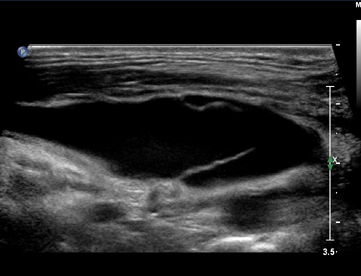

纵断面显示隐—腘静脉汇合处,沿小腿向下扫查小隐静脉主干及其属支。

如果瓣膜功能异常,测量隐—腘静脉汇合处直径,测量隐腘静脉汇合处与腘窝皮肤皱褶之间的距离。